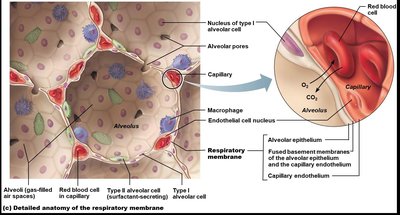

Alveoli are tiny air sacs where gas exchange occurs. They are surrounded by capillaries and have thin walls to facilitate diffusion.

Type I Alveolar Cells: Simple squamous cells forming the respiratory membrane.

Type II Alveolar Cells: Cuboidal cells that secrete surfactant to reduce surface tension.

Alveolar Macrophages: Remove debris and pathogens.

Alveolar Pores: Equalize air pressure and provide alternate air routes.

Gas exchange occurs by diffusion across the respiratory membrane. Oxygen moves from alveoli into blood, while carbon dioxide moves from blood into alveoli to be exhaled.

Respiratory Membrane: Formed by alveolar and capillary walls and their fused basal laminae.

Surfactant: Reduces surface tension, preventing alveolar collapse.